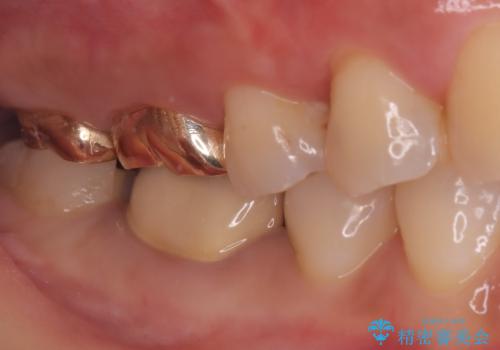

- 主訴:一番奥の歯の奥側の面に虫歯があるのを治したい

クリーニングにいらした患者さんで、右下7番目の歯の奥側の面や手前の歯との間にう蝕があり、噛む面にも蝕処置によるレジン材料が詰まっていたことから、う蝕も古い材料も全て除去しセラミックインレーでのやり替えとなりました。

右下7近遠心にカリエスを認め、咬合面のCR修復も劣化していたので、カリエスと古い材料を全て除去し新しくCR裏層した後、セラミックインレーをセットしています。セット時はラバーダム防湿を行っています。